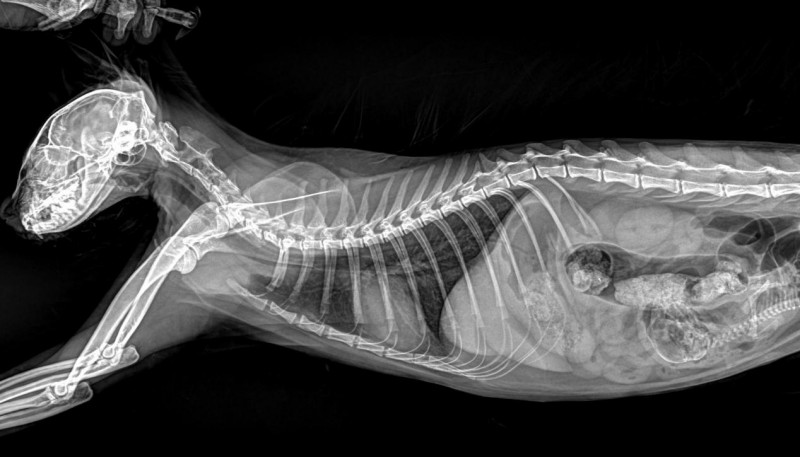

宠物诊疗中,最具挑战性的莫过于细微病灶的诊断——0.1mm的骨骼裂纹、豌豆大小的脏器结节、兔子歪斜过长的臼齿齿根,这些隐匿病灶往往是疾病的关键,却极易被常规DR的模糊图像忽略,导致漏诊、误诊。

必康宠物DR以实测数据彰显高清硬实力:经线对卡实测,成像分辨率均值可达3.7lp/mm,峰值可达4.0lp/mm,远超行业常规标准,细微到0.1mm的骨骼裂纹、脏器微小结节,甚至是纤细如发丝的血管、豌豆大小的淋巴结,都能清晰可辨。临床应用中,无论是小型犬的隐匿性骨折、猫咪的早期骨裂,还是兔子上臼齿牙根异常生长压迫眼球的复杂病例,必康DR都能精准捕捉病灶细节,清晰呈现病变位置、大小与形态,帮助兽医快速锁定病因,为后续治疗筑牢诊断根基。

某宠物医院接诊一只精神萎靡、眼球突出的兔子,疑似严重牙科疾病,常规DR拍摄的影像模糊,无法清晰呈现齿根状态,难以确诊。借助必康宠物DR的高清成像与AI器官分割功能,设备快速捕捉影像,清晰呈现兔子右臼齿的过长、歪斜,以及齿根穿透牙槽骨、压迫眼球后方的细节,AI伪彩增强进一步凸显病变区域,兽医几分钟内便精准确诊,为后续手术治疗争取了宝贵时间,也让宠主看到了希望。